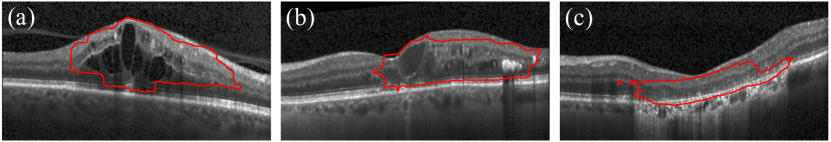

Refer to caption

Figure 5: Qualitative results of the proposed method, on the late wet AMD test set. Central B-scans of volumes in which the proposed method performed best/worst in terms of the Dice index are shown. The corresponding Dice values are 0.82, 0.81, 0.72 and 0.72, from top to bottom. The last column indicates the overlap between the manual annotations of anomaly in green and the prediction of anomaly by our model in red.

Qualitative anomaly segmentation results obtained in the late AMD test set are shown in Fig. 5. The central B-scans, corresponding to the volumes in which our method performed best/worst in terms of Dice, are shown in the top/bottom two rows. An additional example of a non central B-scan is depicted in Fig. 1. Further qualitative results in DME, RVO and GA cases are depicted in Fig. 11 and in the supplementary material.